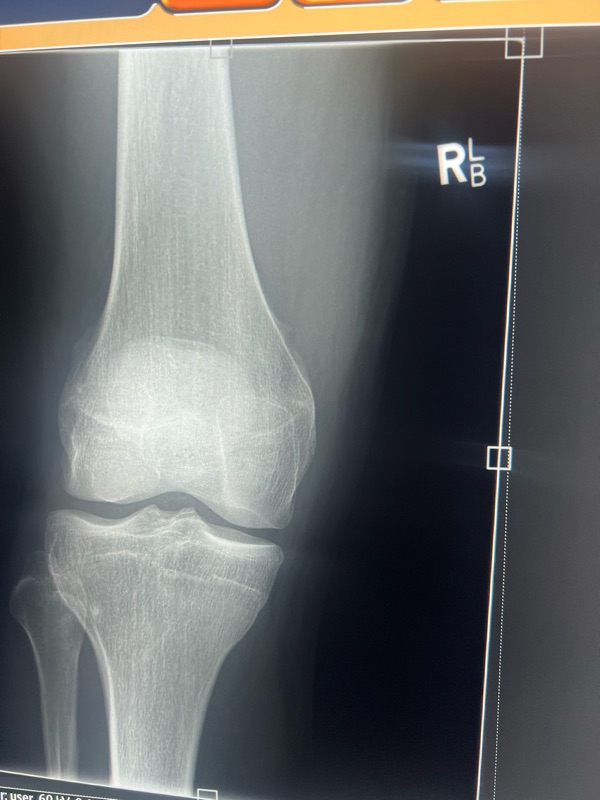

it ended like this! Not amazing but luckily nothing broken. A couple of hours at Mansfield hospital. We left had dinner and met Andrew and Luce at the camp ground and camped the night. Harry was pretty disappointed he didn’t get to race but one’s still a nice weekend away.

Ended like this…